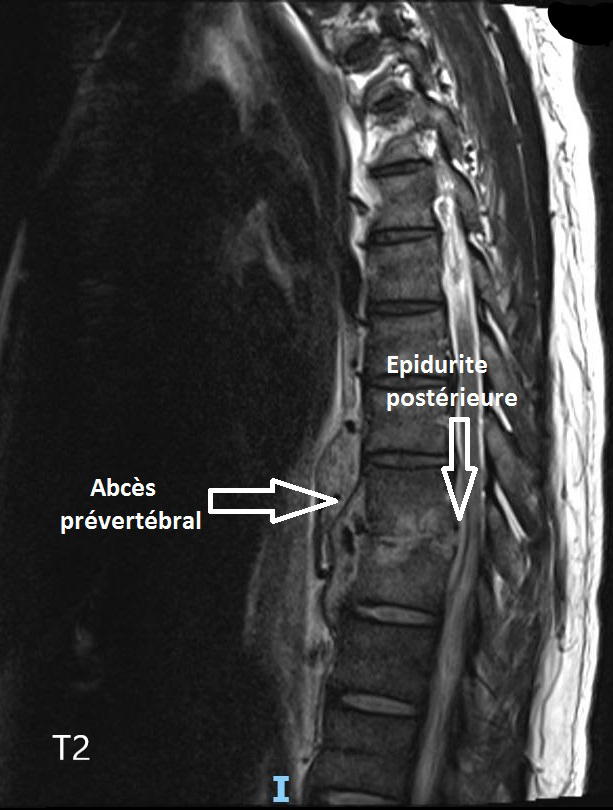

Vous voyez en consultation M. M., 52 ans, pour des douleurs dorsales évoluant depuis quelques semaines. Il est d’origine mauritanienne, travaille dans le bâtiment, et n’a pas d’antécédent particulier, ni de consommation de tabac ou d’alcool. Il ne prend aucun traitement.

Il vient vous voir car il ne peut plus travailler du fait des douleurs qui sont devenues permanentes, y compris la nuit, sans irradiation. Il n’a pas pris sa température mais signale des sueurs nocturnes depuis dix jours. Il a également constaté une faiblesse des membres inférieurs lorsqu’il marche longtemps, l’obligeant à s’arrêter, sans douleur. Il n’a pas de trouble sphinctérien à l’interrogatoire.

Il faut donc évoquer une pathologie rachidienne inflammatoire/infectieuse/tumorale avec syndrome de compression médullaire partiel se traduisant uniquement par une claudication médullaire : celle-ci correspond à un syndrome pyramidal, démasqué par l’effort.